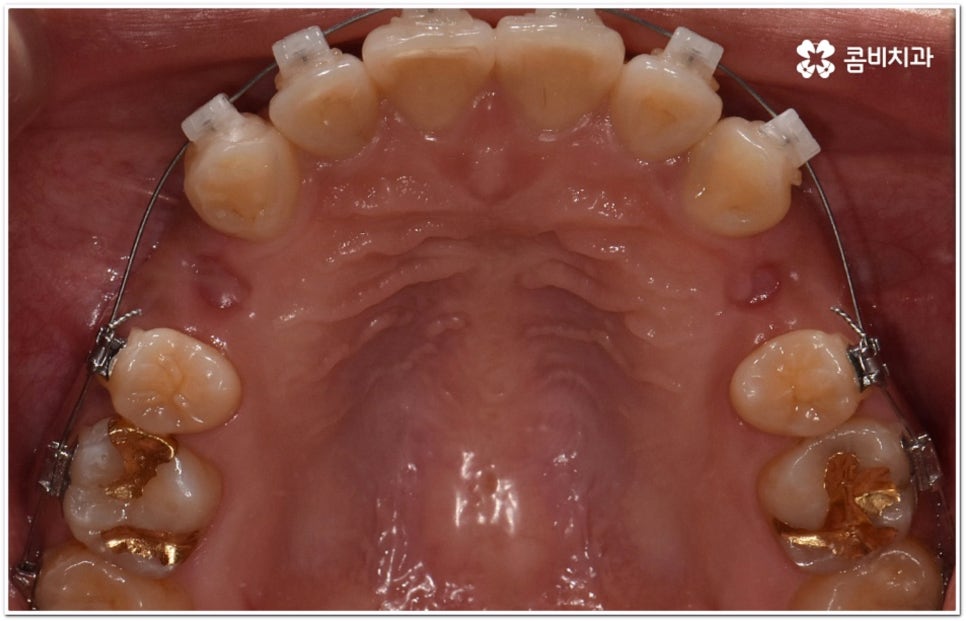

환자마다 치열, 교합, 치아가 튀어나온 각도, 잇몸이 드러나는 정도, 상악과 하악의 구조 및 관계 등 턱관절 관련 부분 상황이 모두 다르기 때문에 3D CT 같은 정밀 검진 기계를 통해 이를 꼼꼼하게 살펴보고 각각에 맞는 계획을 세밀하게 세워 교정 치료를 진행해 줄 필요가 있어요. 이때 환자분들의 상황에 따라 양악수술과 같은 외과적인 방법을 병행해야 하는 케이스도 있을 수 있기 때문에 돌출입을 가지고 계신 분들 중에서 수술에 부담을 느끼고 지레 치료를 포기하신 분들도 있을 수 있는데 정도가 많이 심각하지 않고 구조적인 원인이 크지 않다면 대부분의 케이스는 치아교정 만으로도 충분히 개선이 가능하니 먼저 돌출입교정치과 에 들러서 정밀 검사를 진행한 후 치료 방향에 대해 의료진과 논의해 보시면 좋을 거예요.

말씀드렸던 것처럼 돌출입의 원인이 치아 만의 문제, 즉 각도가 살짝 앞으로 뻐드러진 데 있고 상태가 그다지 심한 것 같지 않다면 보다 빠르고 간편한 수복이 가능할 수 있어요. 튀어나온 부분을 집어넣기 위해서는 발치가 필수적이지 않을까 생각하실 수 있는데 후방으로 이동시켜 줄 공간이 충분하다면 치간 삭제, 악궁 확장, 어금니 후방 이동 등 다른 방법을 이용하여 비발치 치료 과정을 진행할 수 있으므로 너무 걱정하지 않으셔도 될 거예요. 오히려 환자분들의 다양한 상황을 고려하지 않고 무리하게 발치 교정을 진행하게 되면 옥니나 합죽이와 같은 부작용이 일어날 수도 있기 때문에 원인을 정확하게 파악하고 적절한 치료를 할 수 있도록 임상 경험이 풍부하고 뛰어난 노하우를 가지고 있는 숙련된 의료진에게 교정 치료를 맡기시는 것이 굉장히 중요하다고 할 수 있습니다.